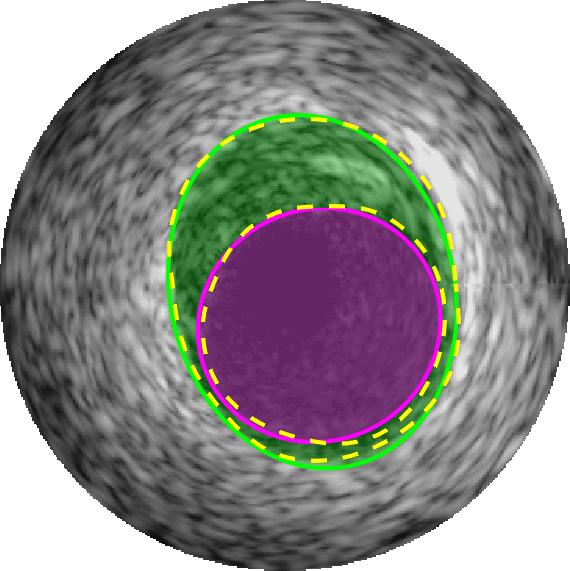

Qualitative evaluations are illustrated in Figure 4 and show the successful segmentation results of the proposed EREL selection strategy for 20 IVUS frames. The lumen areas are highlighted by the magenta colour while the media regions are green. Also, the manually annotated contours for both lumen and media are drawn as yellow dashed lines. As we can see, the chosen frames contain a variety of lumen and media morphologies.